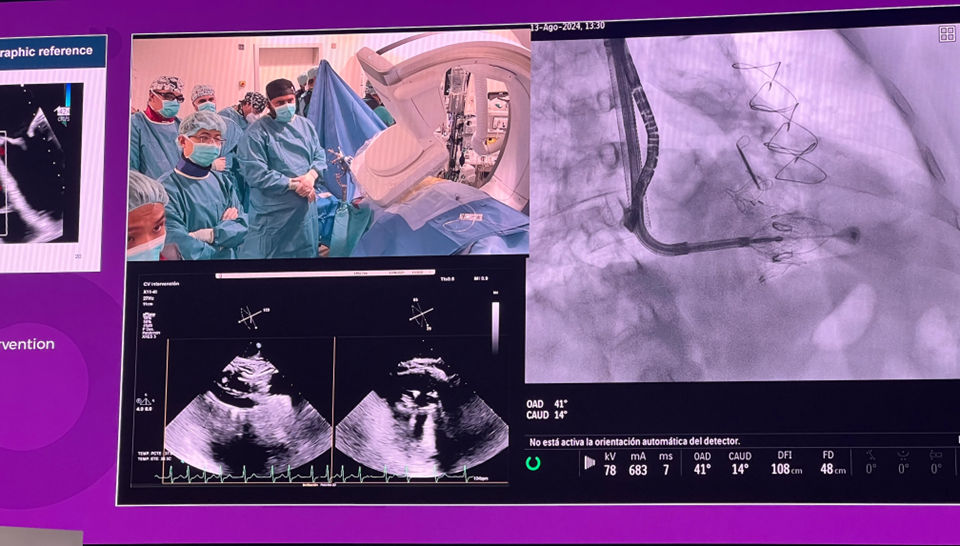

Part 02.  經(jīng)導(dǎo)管介入瓣膜新技術(shù)——來自西班牙維哥的LuX-Valve Plus手術(shù)錄播

隨后由來自西班牙維哥-阿爾瓦羅昆奎羅醫(yī)院(Hospital Álvaro Cunqueiro, Vigo, Spain)的 Rodrigo Estevez-Loureiro 教授在大會主會場的經(jīng)導(dǎo)管介入瓣膜新技術(shù)環(huán)節(jié),帶來了一例 LuX-Valve Plus 手術(shù)錄播,對手術(shù)植入的步驟和關(guān)鍵要點進行了詳細深入的介紹。同時,臺上的多位討論嘉賓也結(jié)合他們的 LuX-Valve Plus 手術(shù)經(jīng)驗進行了深入的探討。來自香港瑪麗皇后醫(yī)院(Queen Mary Hospital, Hong Kong, China)的 Simon Lam 教授分享了 LuX-Valve Plus 在術(shù)前有起搏導(dǎo)線病人中的植入經(jīng)驗,來自巴西圣保羅(Rede D'Or São Luiz, São Paulo, Brazil)的 Vinicius Esteves 教授補充了 LuX-Valve Plus 獨特的非徑向支撐力設(shè)計,能夠?qū)崿F(xiàn)非常低的術(shù)后起搏器植入率,來自法國波爾多大學(xué)醫(yī)院(CHU de Bordeaux, Bordeaux, France)的 Lionel Leroux 教授則分享了其在LuX-Valve Plus歐洲臨床試驗過程中,對于大尺寸瓣環(huán)植入的優(yōu)異結(jié)果。